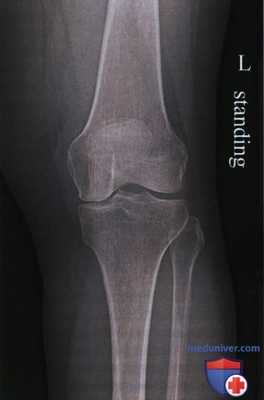

Передне-задняя рентгенограмма коленного сустава: характерная картина, при которой головка малоберцовой кости занимает в некоторой степени задненаружное положение относительно латерального мыщелка большеберцовой кости. Боковая рентгенограмма: межмыщелковая вырезка, которая определяется по линии Блуменсаата (Blumensaat). Медиальный мыщелок бедренной кости несколько крупнее латерального. Латеральный мыщелок бедренной кости может быть также идентифицирован по наличию борозды латерального мыщелка в его передней нагружаемой области. Боковую рентгенограмму получают обычно в положении небольшого сгибания. Обратите внимание на задний наклон поверхности большеберцовой кости, который должен составлять примерно 10°. Аксиальная рентгенограмма: коленный сустав в положении сгибания 20° (состояние максимального подвывиха надколенника). Обратите внимание, что латеральная фасетка надколенника вытянута и имеет менее острый угол, чем медиальная. Описано множество фасеток надколенника, однако медиальная и латеральная имеют наибольшее клиническое значение.

о Стандартные проекции включают в себя передне-задние проекции в положении стоя, боковые с небольшим сгибанием и аксиальные проекции надколенника при сгибании 20°

• Надмыщелки бедренной кости видны в профиль, мыщелки бедренной кости симметричны

• Межмыщелковое возвышение находится в центре межмыщелковой ямки

• Большеберцовая кость перекрывает половину головки малоберцовой кости (рис. 6-10)

• Суставная щель коленного сустава открыта

• Передний и задний края большеберцовой кости совмещены

• Головка малоберцовой кости визуализируется на 1,25 см дистальнее верхней суставной поверхности большеберцовой кости (рис. 14 и 18)